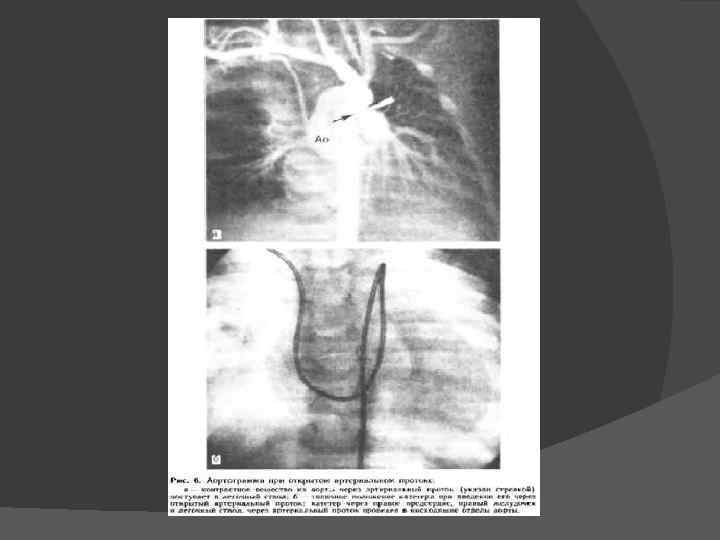

При ангиокардиографии контрастное вещество, введенное в дугу аорты в большой концентрации и в большом количестве, поступает через проток в легочную артерию и в легкие.